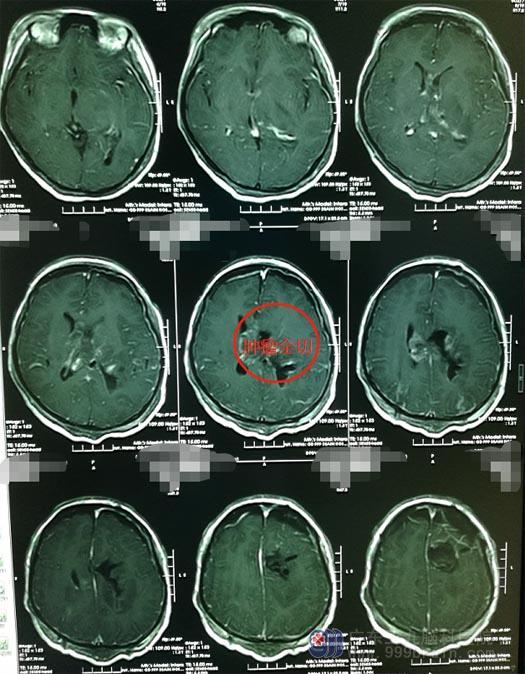

在广东三九脑科医院行头颅MR检查,提示:孟氏孔-双侧侧脑室内占位性病变,大小约7.7cm×5.7cm×5.9cm,考虑中枢神经细胞瘤;头颅CTA示:双侧侧脑室体部巨大占位性病变并出血及钙化,其内血管极其丰富,左侧脉络膜前动脉增粗并供血,伴有粗大引流静脉引流至大脑大静脉。

小云在当地医院已经进行了双侧脑室外引流术。考虑到患者肿瘤巨大,血供丰富,医院副院长、神经外五科主任鲁明建议先行术前放疗,为手术创造有利条件,减少术中出血,提高肿瘤切除程度。急诊放疗后,次日,鲁明带领治疗团队在全麻下行“左侧脑室额角入路左侧脑室及丘脑巨大中枢神经细胞瘤切除术”,术中冰冻结果考虑中枢神经细胞瘤,经过10个小时的奋战,肿瘤被顺利全切。